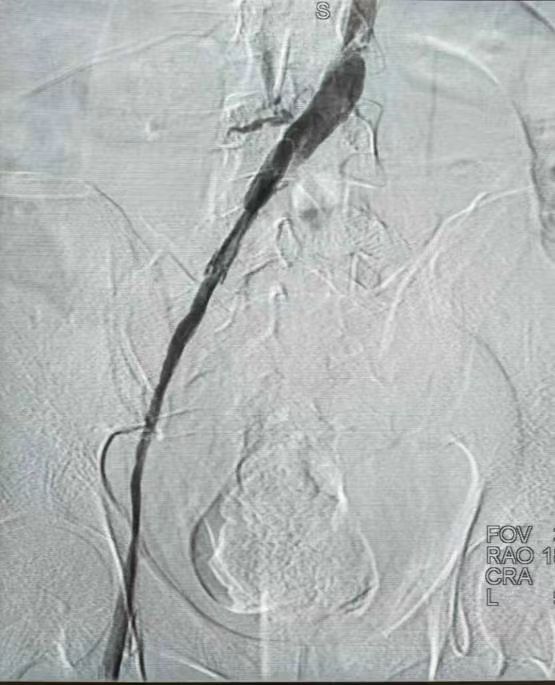

2月10日下午5时许,年轻的井师傅被送到固原市人民医院急诊科,“当时左腿都是黑的、肿的,感觉要炸裂了。”井师傅说。经检查诊断:左下肢深静脉全程血栓+左髂静脉全程闭塞+下腔静脉部分闭塞。通俗地讲,就是从左小腿到大腿一直到肾的水平位置,长达1米的静脉血管严重堵塞,血液无法流通。这条血管界的“连环死胡同”让医护人员大为吃惊,“这么长段的血栓,随时可能脱落,一旦脱落会引发致命肺栓塞,猝死的风险极大”。当晚,医疗团队便采取措施先将下肢堵塞的部分打通,降低生命危险系数,次日再将剩余部分打通。

患者的血栓长达1米。

11日13时,胡育斌带领团队开始了“血管隧道里拆炸弹”的挑战之旅。他们身着厚重的铅衣,进入介入手术室。造影发现即使通过之前的药物溶栓治疗,左侧髂静脉及下腔静脉下段仍然有40厘米长的血栓完全堵塞,这条“血管隧道”被堵得严严实实,而且长得看不到尽头的“光亮”。考虑继续药物治疗无法溶通,“白衣天团”只能凭着多年的经验和高超的介入微创医术“摸黑前行”。他们像“血管清道夫”般,在X射线的引导下,用导丝导管在“血管迷宫”中一寸寸“掘进”。

“光左髂静脉这一段20多厘米长的血栓,就打了1个多小时,下腔静脉这段10多厘米长的血栓,打了半个多小时。”而这半个多小时最惊心动魄,胡育斌顶着辐射贴身操作,在场医护人员纷纷被其精神所感染,“医者仁心”4个字在这一刻被具象化。最终,这场血管里的“毫米级微雕”历时3小时圆满成功,患者血流复通。